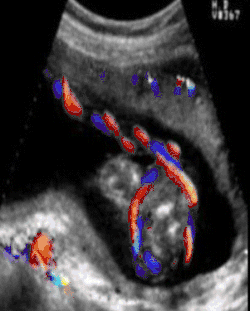

The diagnosis may be suspected if there is a decrease in the baby's heart rate during delivery.[1] Nuchal cords are typically checked for by running the finger over the baby's neck once the head has delivered.[4] Ultrasound may pick up the condition before labor.[1]

Ultrasound diagnosis of a cord around the neck was first described in 1982.[7] “Coils occur in about 25% of cases and ordinarily do no harm, but occasionally they may be so tight that constriction of the umbilical vessels and consequent hypoxia result.” Williams Obstetrics 16th Edition, has only one single sentence in the entire textbook regarding cords around the neck.[8] By contrast, the First Edition of the Encyclopædia Britannica from 1770 had 20 pages of information about Umbilical Cord Pathology with drawings of Umbilical Cord Entanglement. The Royal College of Obstetricians and Gynaecologists has these images on its brochure. There are currently three recent texts on ultrasonography which demonstrate the ability of ultrasound to identify umbilical cord issues with reliability as of 2009.

A study published in 2004 was done to establish the sensitivity of ultrasound in the diagnosis of a nuchal cord. Each of 289 women, induced the same day, underwent a transabdominal ultrasound scan with an Aloka 1700 ultrasound machine with a 3.5 MHz abdominal probe, using gray-scale and color Doppler imaging immediately prior to induction of labor. Presence of the cord was sought in the transverse and sagittal plane of the neck. A nuchal cord was diagnosed if the cord was visualized lying around at least 3 of the 4 sides of the neck. A cord was actually present at delivery in 52 of the 289 women. Only 18 of the 52 cords or 35% of the nuchal cords were detected on ultrasound done immediately before delivery, and 65% of nuchal cords were not detected. Of the 237 cases where there was no cord at delivery, ultrasound had false positive results, i.e. diagnosed a cord in 44 of the 237 cases (19%) in which there was no cord present at all. In this study, ultrasound was only 35% accurate at finding a single loop, and only 60% accurate at detecting a nuchal cord wrapped multiple times around the neck.[9]

In no study was it possible by ultrasound to distinguish between a loose or a tight cord, although at least 3 attempted to do so. Peregrine[9] concludes that ultrasound diagnosis of nuchal cords will only be useful if doctors are able to do so reliably and predict which of those fetuses are likely to have a problem. However, perinatologists routinely look for umbilical cord issues in monoamniotic twins. Studies have shown an improvement in outcomes where cord entanglement was prenatally identified in these cases. Ultrasound measurement of the velocity of flow in the cord may be useful in the management of twins and chronically growth-retarded fetuses. Of course this depends on the training of the sonographer. To date there are no ultrasound courses which teach the identification of nuchal cord to physicians or technicians. A recent review by Wilson of the American Academy of Ultrasonography Technicians recommends the documentation of umbilical cord issues.[10]